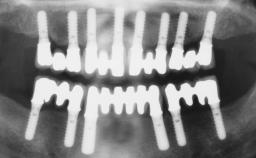

Conventional Loading of Six Implants in the Mandible and Final Restoration with a Full-Arch Metal-Ceramic FDP

# of Implants 6

Type of Implants One-Piece

Defining Characteristics Fully edentulous lower jaw to be rehabilitated with two or more implants

Modality > 4 implants, extending to mental nerve region

Defining Characteristics Fully edentulous lower jaw to be rehabilitated with an implant-borne fixed dental prosthesis

Retention Screw-retained, with 4 or more splinted implants Screw-retained, with 4 or more splinted implants